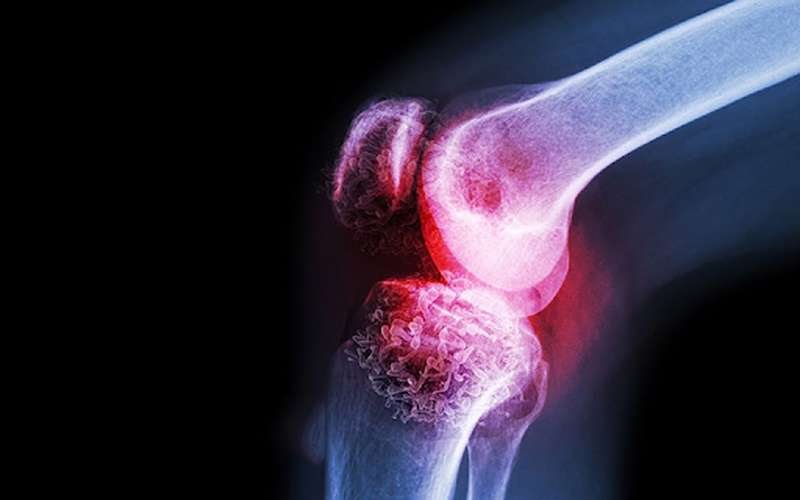

Tìm hiểu chung: Dấu hiệu của U xương ác tính 2 Bệnh Paget là dấu hiệu của u xương ác tính

• Bệnh Paget: Là tình trạng khiến xương bị gãy và sau đó nó phát triển trở lại một cách bất thường.

• Mắc các bệnh u xương lành tính có nguy cơ chuyển sang ác tính như: Bệnh loạn sản xương, bệnh Paget xương.

• Theo dõi sát các bệnh nhân mắc các bệnh u xương lành tính hay Paget xương để tránh trình trạng dẫn đến u xương ác tính.